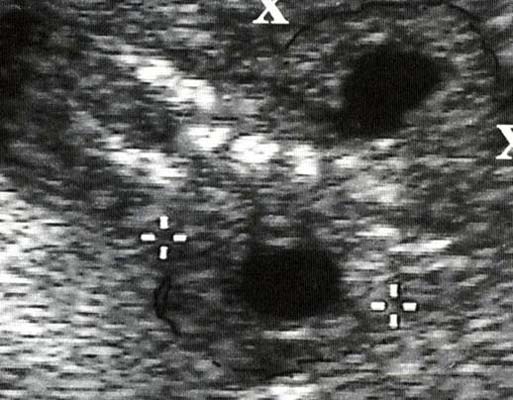

- Sur une coupe transversale, diamètre antéro-postérieur du bassinet > nombre de mois X 1 mm, calices plus ou moins visibles.

- Diamètre entre 4 et 10 mm : Pyélectasie modérée

Diamètre > 10 mm : Hydronéphrose